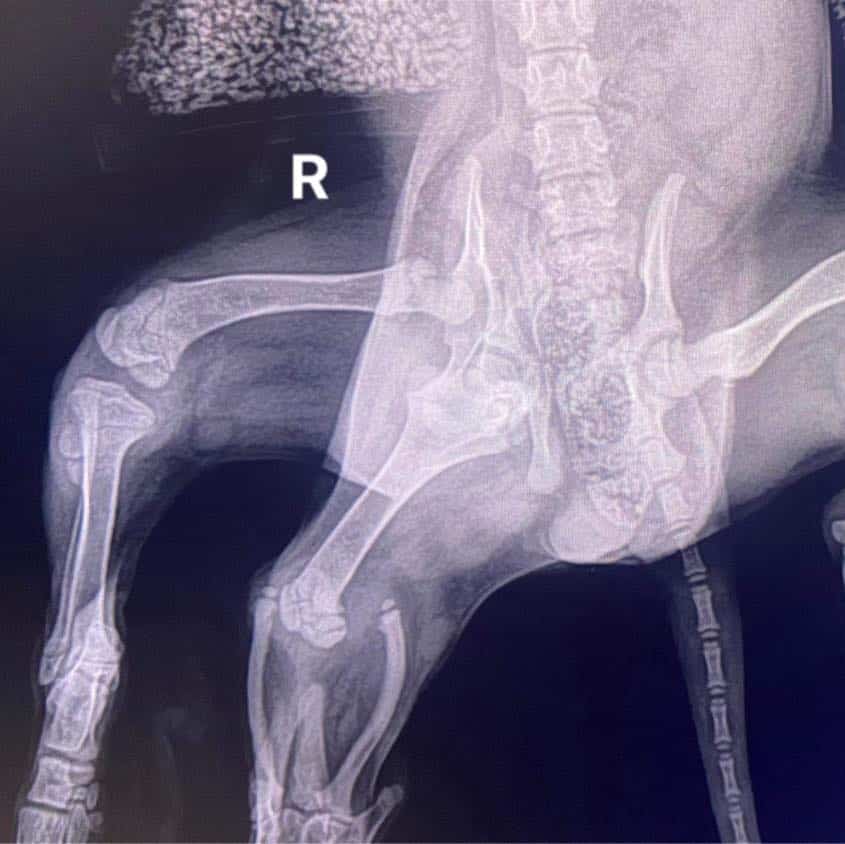

เขาอธิบายถึงผลเอ็กซเรย์ขาของแอเรียลว่า ‘ขาส่วนเกินทั้งสองที่ติดกันงอกขึ้นมาบริเวณฝั่งขวาของหางของแอเรียล’ จากนั้นกล่าวต่อว่า ‘โดยพื้นฐานแล้วกระดูกต้นขา 1 อันจะแยกออกเป็นกระดูกหน้าแข้ง 2 ส่วนที่ข้อเข่า แต่พวกมันใช้งานไม่ได้และ” ไม่มีประโยชน์อะไรเลย’

‘ผลเอ็กซเรย์แสดงให้เห็นความผิดปกติของมัน แต่สัตวแพทย์ที่ยอดเยี่ยมของเรามั่นใจว่าเราสามารถแก้ไขปัญหานี้ได้’